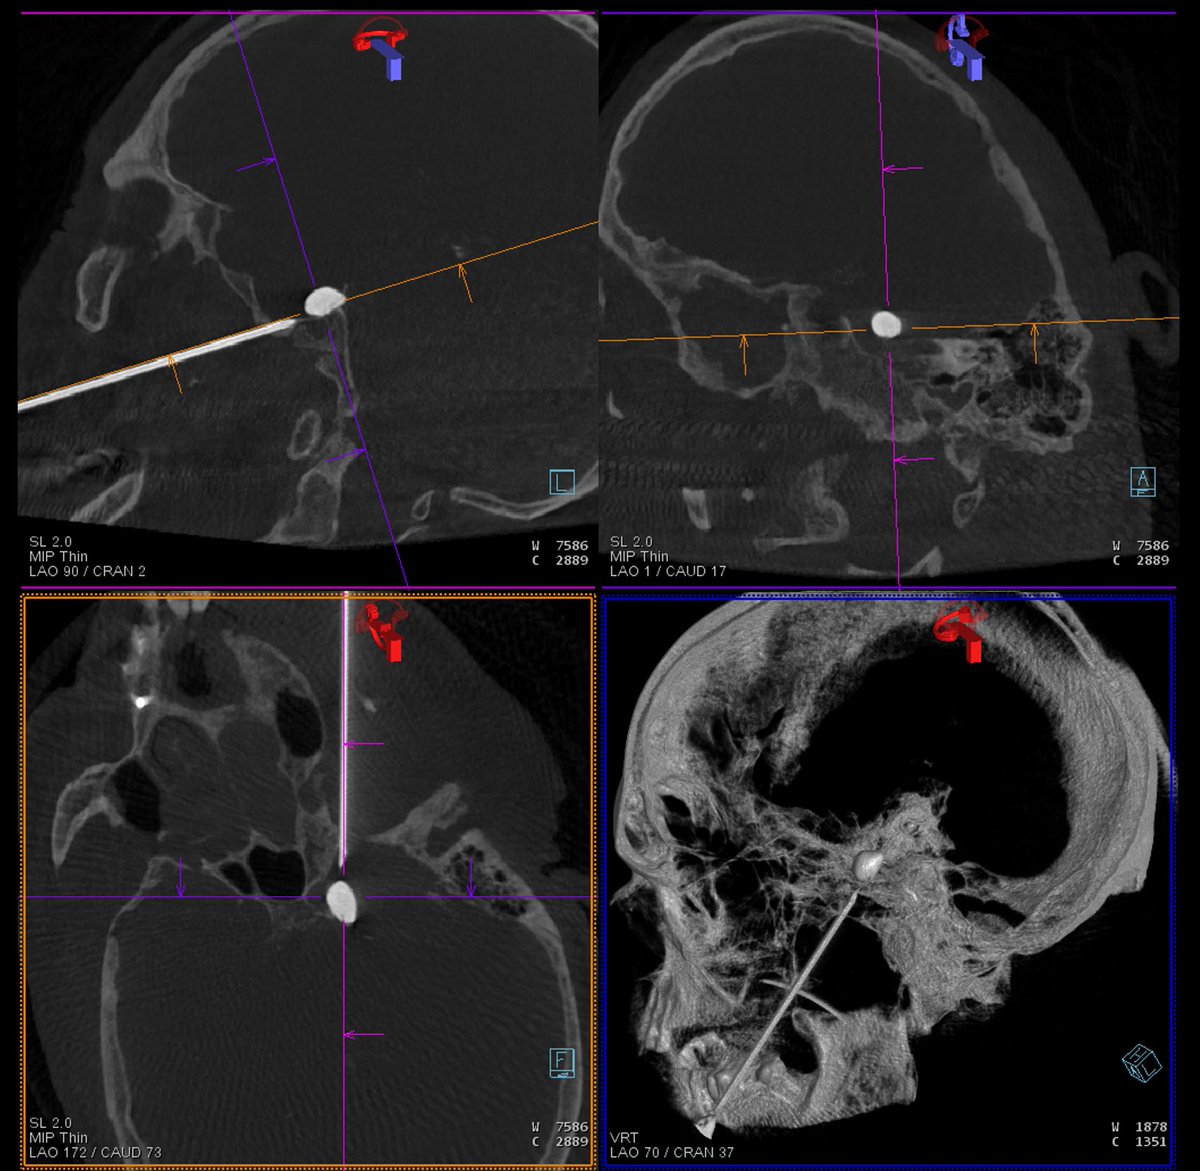

Using

#biplane#angiosuite for#percutaneous#balloon#rhizotomy in#trigeminal#neuralgia. Great imaging improves accuracy and decreases procedural time.#TrigeminalNeuralgia#TrigeminalNeuralgiaAwarenessDay https://jnis.bmj.com/content/6/9/699@JNIS_BMJpic.twitter.com/lU0F7Ubs79